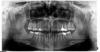

IvanK Опубликовано 8 июля, 2013 Поделиться Опубликовано 8 июля, 2013 Доброго всем дня! Вчера удалили зуб 5-ку. Позже буду ставить имлант. Чтобы закрыть пустое место врач предлагает обточить 6-ку (6-ка кандидат под коронку) и надеть временную коронку, либо сделать съемный протез. Как лучше?я не советую делать что-то съемное...14, 26 и 36 - перелечивание + коронки 28 на удаление Ссылка на комментарий